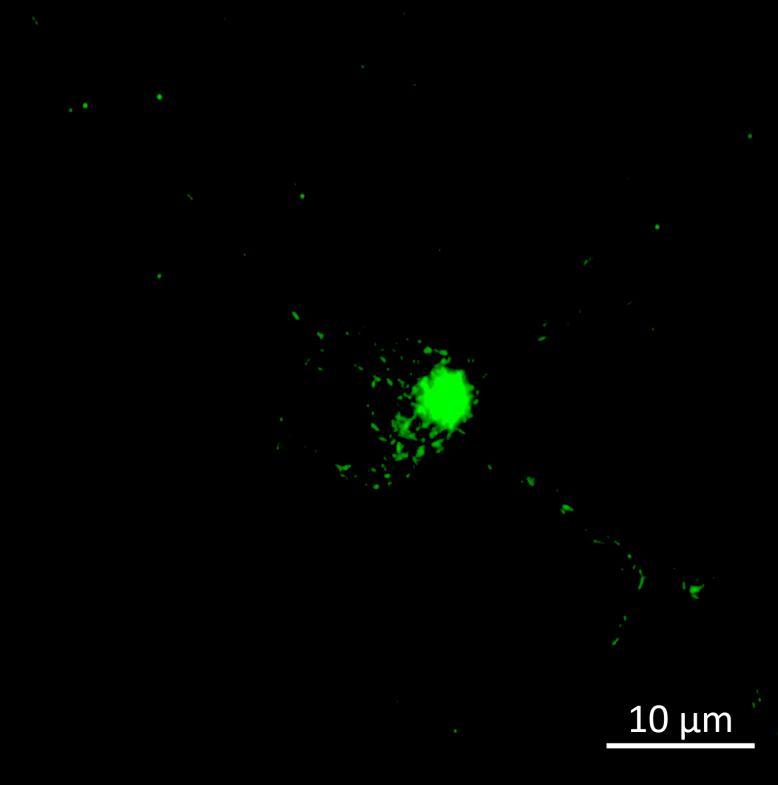

• Isogenic control and early onset Parkinson’s disease SNCA A53T mutation neurons were exposed to α-synuclein PFFs with A53T mutation

• Neurons were fixed and labelled for α-synuclein phosphorylated at serine 129 (pS129)

• PFF treated neurons show Lewy body-like perinuclear aggregates of pS129 α-synuclein